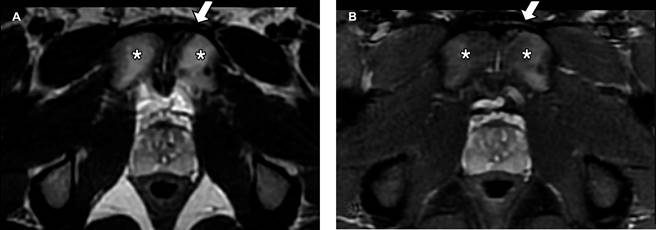

Se realizó ultrasonido inguinal y radiografía anteroposterior de pelvis las cuales no mostraron alteraciones; posteriormente, se decidió realizar resonancia magnética de pubis: en plano coronal (Figura 1) se observó fractura vertical en el cuerpo del hueso púbico izquierdo (flecha blanca en A y B) con edema de tejidos blandos adyacente (asterisco en A y B); en plano axial (Figura 2) se identificó fractura en la porción anterior del cuerpo del hueso púbico izquierdo (flecha blanca en A y B), existe osteítis púbica bilateral de predominio izquierdo (asterisco en A y B) y en plano sagital (Figura 3) se observó edema óseo a nivel de la placa aponeurótica del recto abdominal y aductor largo bilateral (flecha amarilla en A y B) de predominio izquierdo; además de desgarro en la placa aponeurótica izquierda (flecha verde).

Figura 2: Resonancia magnética de pubis. A) T2 plano axial. B) plano axial STIR. Se identifica trazo de fractura en la porción anterior del cuerpo del hueso púbico izquierdo (flechas blancas en A y B), existe osteítis púbica bilateral de predominio izquierdo (* en A y B).